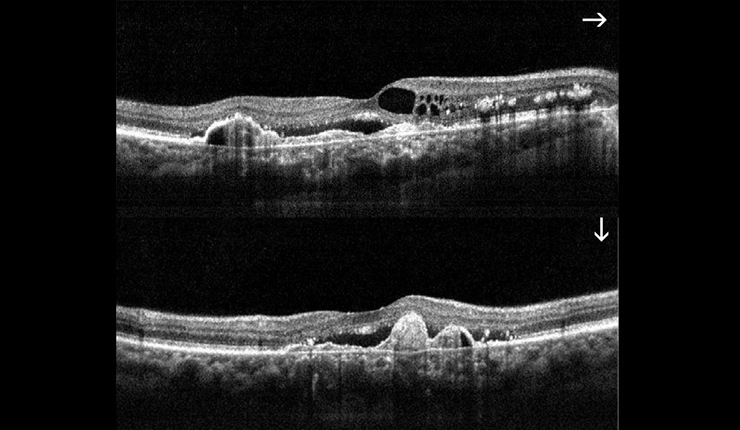

AMD. High resolution horizontal and vertical scans showing cystoids oedema, CNV, RPE proliferation and sub retinal fluid at the fovea.